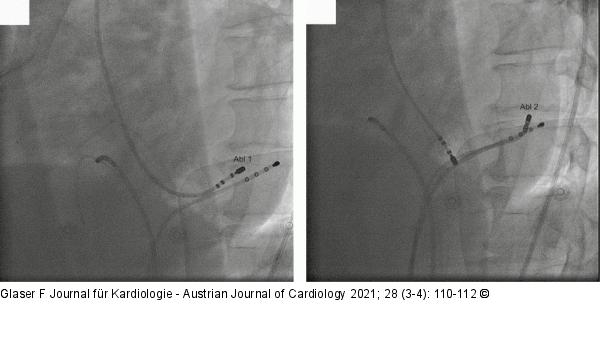

Abbildung 3: Ablation Ablationssitus: 60° LAO-Projektion: Links: Endokardiale Ablation über retrograden aortalen Zugang (Abl 1). Rechts: Epikardiale Ablation über Coronarsinus (Abl 2). |

Ablationssitus: 60° LAO-Projektion: Links: Endokardiale Ablation über retrograden aortalen Zugang (Abl 1). Rechts: Epikardiale Ablation über Coronarsinus (Abl 2). |